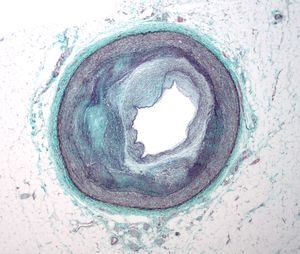

يمكن اعتبار مرض تصلب شرايين القلب مجموعة من الأمراض التي تصيب القلب. واحدة من هذه صور هذا المرض هو شخص بلا أعراض وجدران شرايين قلبه التاجية مبطنة من الداخل بخطوط من الدهون atheromatous streaks. يمثل ظهور هذه الخطوط المرحلة الأولى من مرض القلب التاجي ولكنها لا تعيق تدفق الدم خلال الشريان. إذا تم عمل تصوير الشرايين التاجية Coronary Angiogram خلال هذه المرحلة من المرض فانه من المحتمل ألا يظهر أي دليل على وجود مرض تصلب الشرايين القلبية وذلك لان قطر تجويف الشريان لم يقل. خلال عدة سنوات، تزداد هذه الخطوط الدهنية سماكة، وازدياد سماكتها مبطِنة جدار الشريان يؤدي في النهاية إلى صغر تجويفه وبالتالي يعوق مسار الدم خلاله. اُعتقد في السابق أن عملية تكوّن الصفائح الدهنية عملية بطيئة وتدريجية، لكن ظهرت دلائل حديثة على أن التكون التدريجي لهذه الصفائح يُسرّعُه تمزقات صغيرة تحدث فيها مما يؤدي إلى ازدياد حجم الصفيحة الدهنية نتيجة تراكم المواد المتخثرة عليها. من النادر أن تسبب الصفائح الدهنية التي تسد أقل من 70 في المائة من تجويف الشريان أعراض مرض انسداد الشرايين التاجية. في حال ازدياد حجم الصفيحة مسببة انسداد الشريان بنسبة تزيد عن 70 في المائة، تظهر في الشخص في هذه المرحلة أعراض انسداد الشرايين التاجية. يمكن القول في هذه المرحلة من المرض أن الشخص لديه مرض نقص التروية القلبية ischemic heart disease. تُلاحظ أولى أعراض مرض نقص التروية القلبية خلال الأوقات التي يزيد فيها الضغط على عمل القلب. كمثال على ذلك، الم الذبحة الصدرية الجُهدية exertional angina أو تراجع قدرته على تحمل التمارين البدنية. قد يتطور المرض فيما بعد ليصل إلى الحد الذي يُسد فيه تجويف الوعاء الدموي بشكل شبه كامل، معيقاً وصول الدم حامل الأكسجين إلى عضلة القلب. المصابون بهذه الدرجة من مرض الشريان التاجي يكونون قد عانوا من جلطة قلبية (ذبحة صدرية) مرة أو اثنتان، وقد يكون لديهم أعراض أو علامات مرض الشريان التاجي المزمن، متضمنا الم الذبحة الصدرية بدون أي مجهود بدني angina at rest أو الاستسقاء الرئويflash pulmonary edema. يجب أن يتم التمييز بين كلٍ من مرض نقص التروية القلبية myocardial ischemia والجلطة القلبية (احتشاء عضلة القلب) myocardial infarction. نقص التروية معناه أن كمية الأكسجين التي تصل إلى عضلة القلب غير كافية لتلبية احتياجه. عندما تنقص تروية عضلة القلب فإنها لا تعمل بالشكل الأمثل، وإذا نقصت التروية لمساحة كبيرة من عضلة القلب فان ذلك قد يؤدي إلى عدم قدرة العضلة على الانقباض والانبساط. إذا تحسن تدفق الدم إلى العضلة فان نقص التروية يمكن عكسه. بينما الجلطة القلبية معناها أن نسيج العضلة قد مات ولا يمكن عكس ذلك لقلة تدفق الدم المشبع بالأكسجين إليها. قد يحدث للشخص تمزق للصفيحة الدهنية في أي مرحلة من مراحل المرض. التمزق المفاجئ للصفيحة قد يؤدي إلى جلطة قلبية مفاجِئة (ذبحة صدرية).

فيسيولوجية مرضية خاصة

تحدث أمراض القلب التاجية عندما تصاب الطبقة العضلية المرنة في الشرايين التاجية _ الشرايين التي تغذي القلب _ بتصلب الشرايين. مع تصلب الشرايين تقسو بطانة الشرايين وتتيبس وتنتفخ بكل أنواع "الـترسبات"، شاملة ترسبات الكالسيوم، وتراكمات الدهون وخلايا التهابية غير سوية ليكونوا معًا صفيحة. هذه الصفائح تشبه بثرة كبيرة تبرز إلى قناة الشريان مسببة انسداد جزئي يعيق تدفق الدم. يختلف عدد هذه الصفائح عند المصابين بأمراض القلب التاجية فبعضهم يملك فقط صفيحة واحدة أو اثنتين والبعض الآخر قد يعاني من دزينة من الصفائح موزعة في الشرايين التاجية. متلازمة X القلبية مصطلح طبي يصف الانزعاج والخناق والألم الصدري لدى بعض الأشخاص بالرغم من أن رسم الأوعية التاجية لهم لا يظهر أي علامات لوجود أي انسداد في الشرايين التاجية الكبيرة. ما يزال مسبب متلازمة X القلبية الدقيق مجهولا لكن من المستبعد أن يكون وراءها سبب واحد فقط. اليوم، أصبحنا نعرف أن العامل الرئيسي المسبب للمتلازمة هو الاختلال الوظيفي في الأوعية الدموية بالغة الصغر والتي تعني هنا الشريينات والشعيرات الدموية المغذية للقلب.أظهرت الدراسات أيضا أن الإدراك الحسي للألم لدى المصابين بمتزامنة X القلبية _ وغالبا من النساء _ معزز، مما يعني أنهم يشعرون بآلام الصدر بشكل أكثر شدة وكثافة مما يشعر به غيرهم.